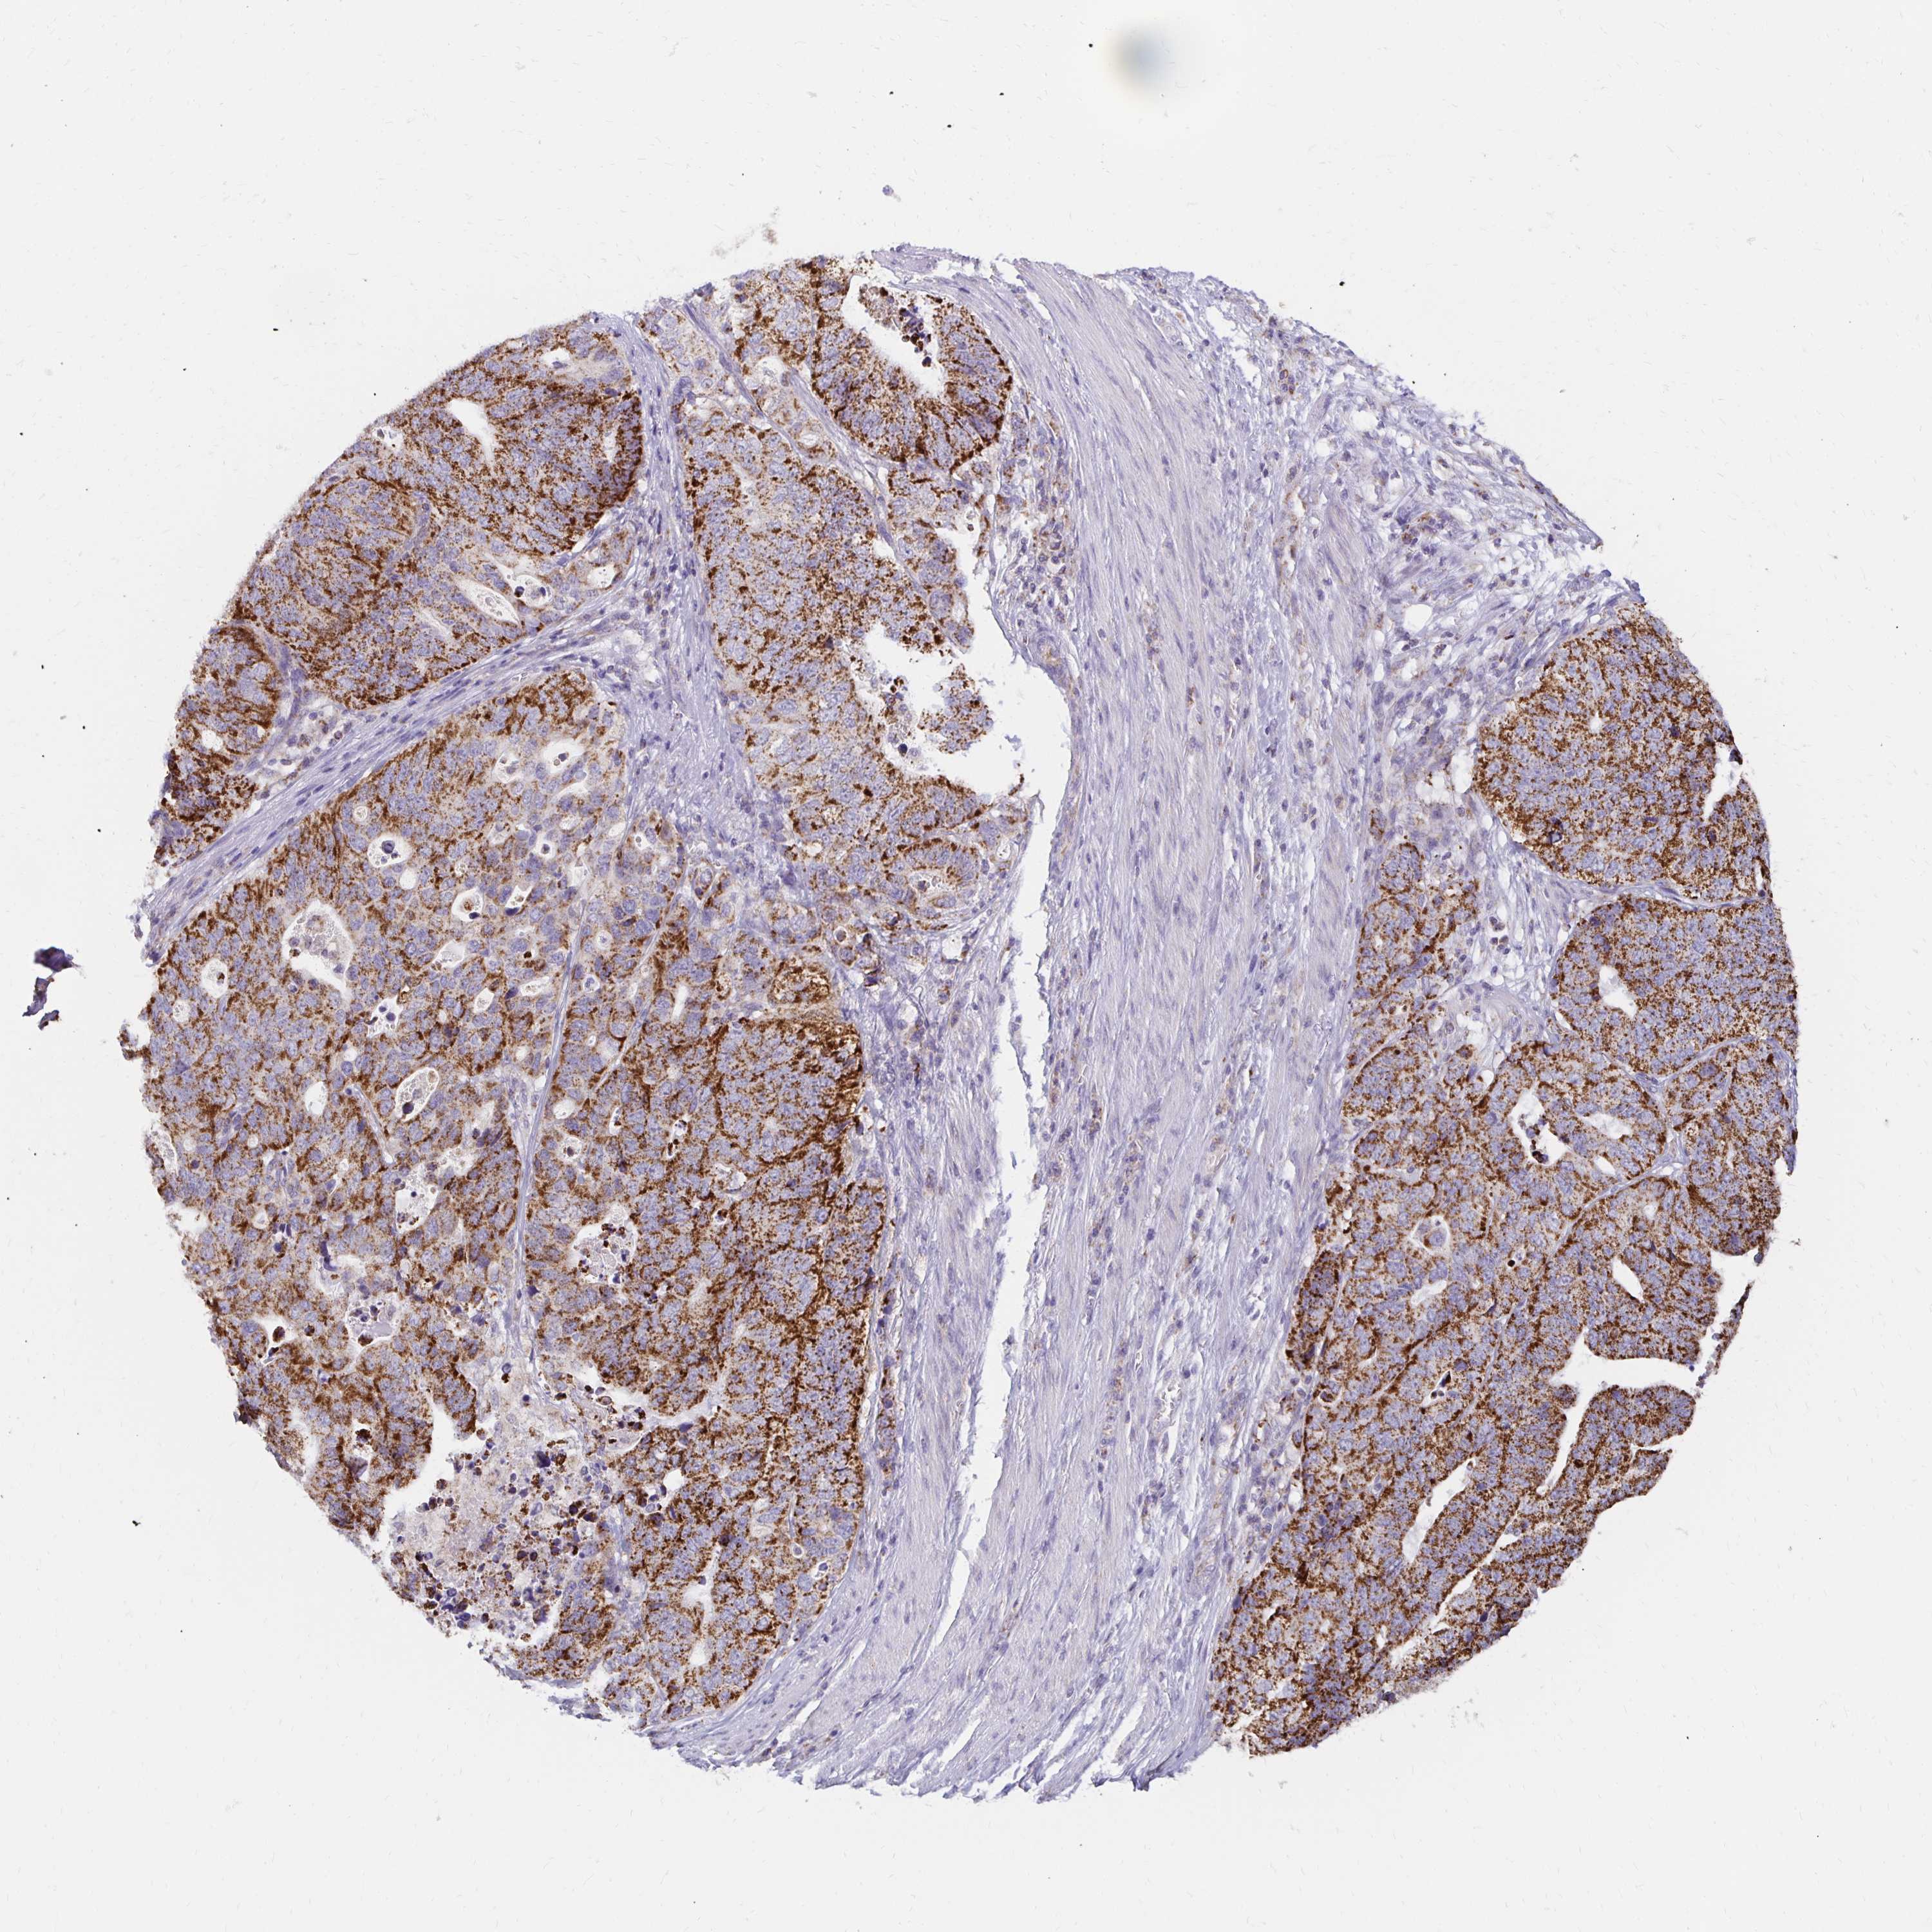

STOMACH CANCER - Protein expressioni

A mouse-over function shows sample information and annotation data. Click on an image to view it in a full screen mode. Samples can be filtered based on level of antibody staining by selecting one or several of the following categories: high, medium, low and not detected. The assay and annotation is described here.

Note that samples used for immunohistochemistry by the Human Protein Atlas do not correspond to samples in the TCGA dataset.

Antibody stainingi

Antibody staining in the annotated cell types in the current human tissue is reported as not detected, low, medium, or high, based on conventional immunohistochemistry profiling in selected tissues. This score is based on the combination of the staining intensity and fraction of stained cells.

Each image is clickable and will lead to virtual microscopy that enables deeper exploration of all samples and also displays staining intensity scores, fraction scores and subcellular localization as well as patient and tissue information for each sample.

Antibody HPA043847

Staining

High

Medium

Low

Not detected

Intensity

Strong

Moderate

Weak

Negative

Quantity

>75%

75%-25%

<25%

None

Location

Nuclear

Cytoplasmic/membranous

Cytoplasmic/membranous,nuclear

Adenocarcinoma, NOS